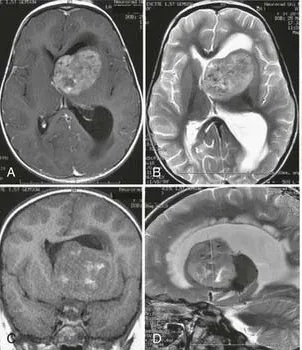

INC国际儿童脑瘤专家、《Child's Nervous System》现任主编Concezio Di Rocco教授团队于2009年发表研究《5-YEAR-OLD BOY WITH A CLIVAL MASS》,报道首例儿童斜坡区上皮样肉瘤病例。...